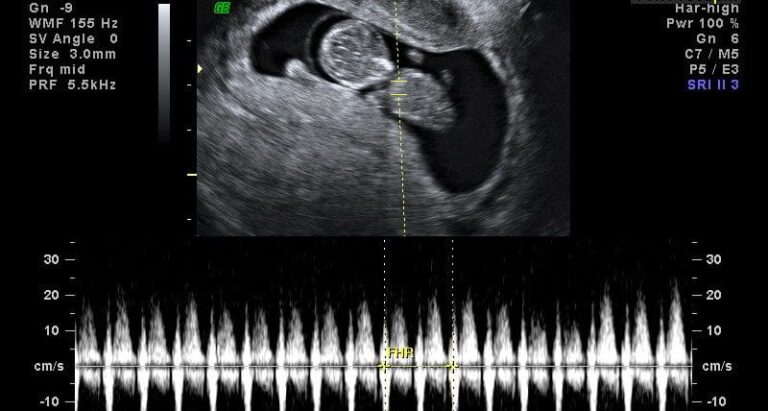

Qual é a frequência cardíaca normal do feto?

Esta é uma pergunta que você provavelmente tem desde a primeira vez que você ouviu bater o seu…